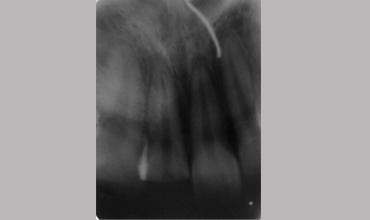

Management Of Fractured Tooth With Cast Post & Core